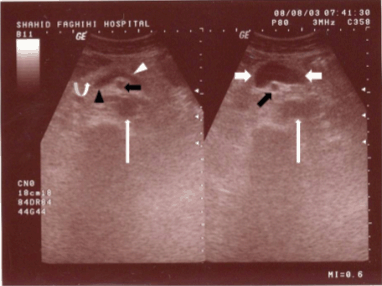

A 73-year-old female came to our sonogrphic clinic for abdomino-pelvic sonography as a routine work-up. In her medical history she had positive history of mild hyperlipidemia and mild essential hypertension and was on ß-blocker, nitroglycerine and anti-lipid therapy. Routine workup (CBC, LFT) was normal. She had no history of abdominal trauma or liver disease. Incidentally, on evaluation of para-aortic area, an anechoic structure was noted anterior to inferior vena cave (IVC) which was in continuation to portal confluence and was in the region of superior mesenteric vein (Figure 1). There was no sign of portal hypertension. Liver and spleen were normal (Figure 2). Color doppler flow mapping revealed flow inside the structure (Figure 3). Spectral analysis further confirmed venous type flow in this region (Figure 4). These findings confirmed the diagnosis of superior mesenteric vein aneurysm.

Figure 2: Abdominal ultrasonography (GE Healthcare logic 500 convex probe 3.5 MHz) showed normal size and echo texture of liver (A, between arrows) and spleen (B, between arrows).